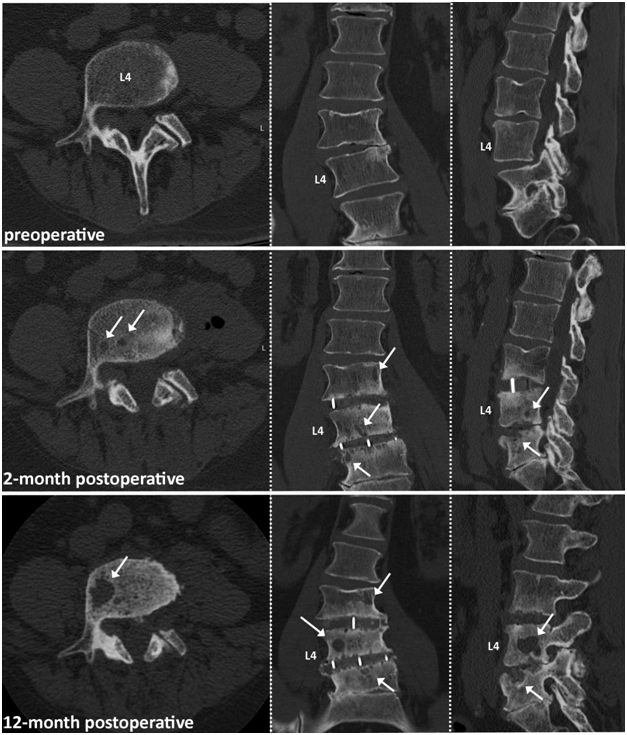

At the time of the reporting, stability was preserved in the remaing two patients and they did not require further surgical treatment to address the osteolytic destructions (Figures 2&3). Total follow-up times for patients were 29, 22, and 6 months, for patient 1, 2, 3 respectively.

Figure 2 64-year old male patient with 2 level LLIF procedure. Note: Patient underwent posterior decompression 6 month prior to LLIF surgery. White arrows indicating starting osteolytic bone destruction at the L3-L4 and L4-L5 vertebra endplates 2 month postoperative. Osteolysis increased over the 12-month postoperative course, with one major big osteolytic cyst in the L4 vertebra.